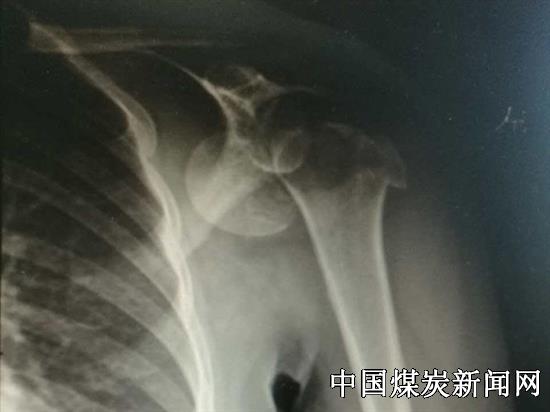

46岁的女性患者陈某,因摔伤后导致左肩部疼痛、肿胀,肩部不能活动,经过X线片检查显示其肱骨头粉碎性骨折并脱位,该院骨六科主治医师郭家全具有丰富的关节创伤治疗经验,受伤的患者预约请他治疗,入住总医院骨六科,在该科主任牛志强大力支持和指导下他积极准备手术器械,认真制定手术计划。对此病例,考虑患者肱骨头粉碎性骨折,大家讨论认为若常规行内固定易失效,且易发生严重并发症,影响肩关节康复,最后决定为其行肩关节置换术。

肩关节置换术在总医院南院区还未开展过,郭家全根据诊断结果认真实施手术的每个细节,在术中患者出血仅200毫升,按计划顺利完成手术。术前,这位肩关节粉碎性骨折的患者入院时听说需换假关节,非常担忧、害怕甚至痛哭;术后,随着慢慢康复逐渐恢复了肩关节的功能,她露出了开心的笑容。出院时,患者不住地为总医院南院区骨六科关节诊治技术点赞。